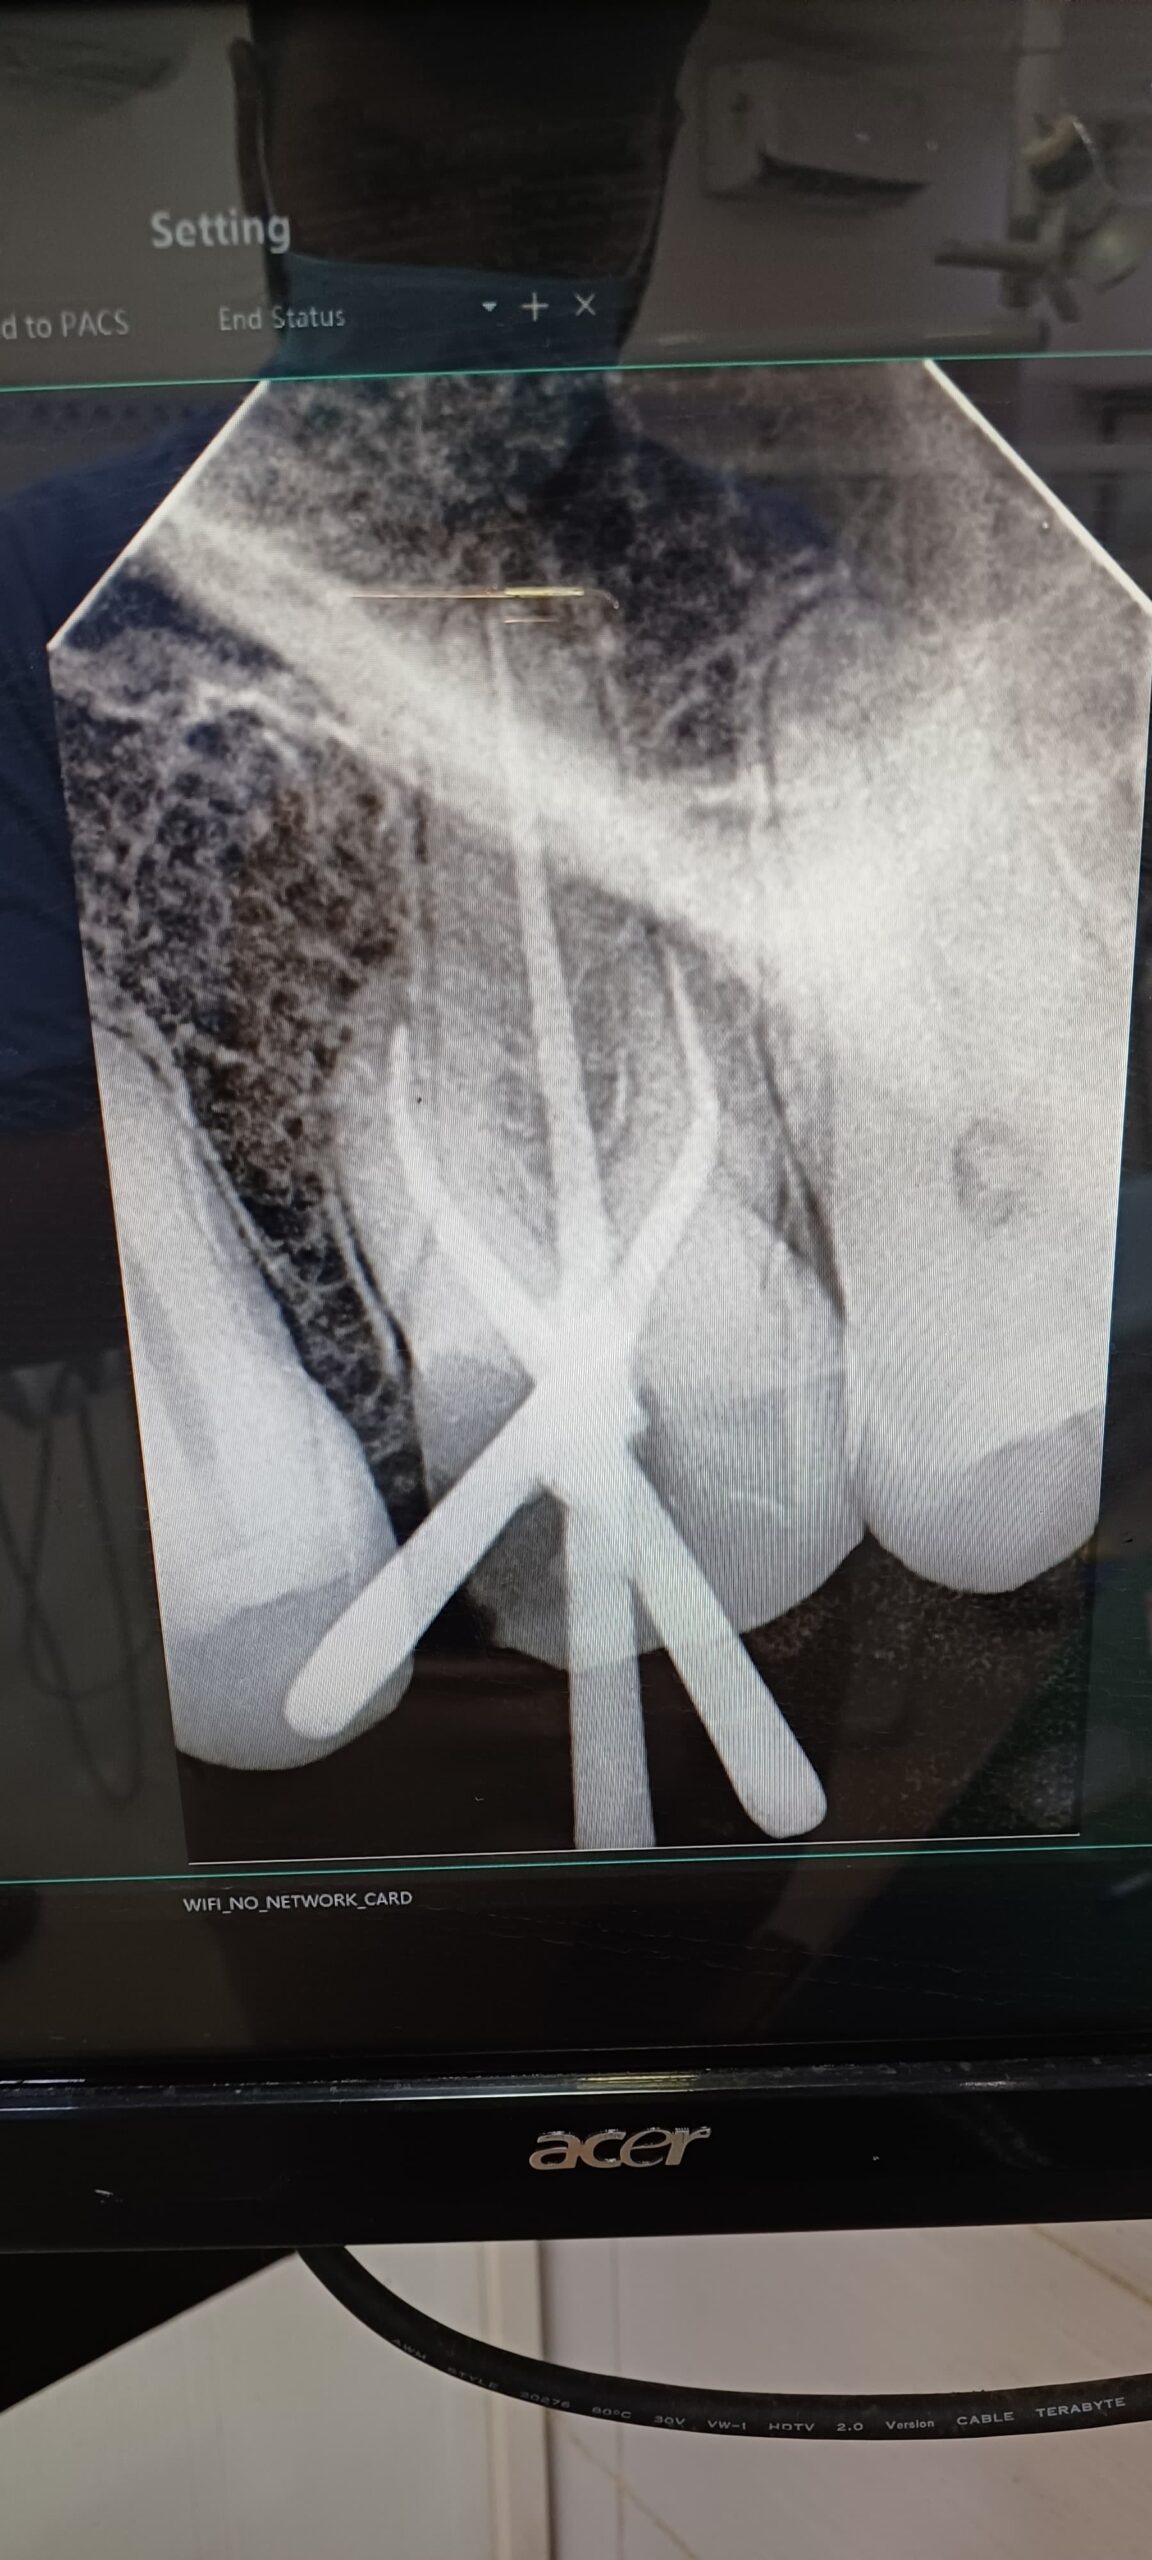

Gallery Home Gallery Pulpectomy Broken File Retrieval Root Canal Treatments Orthodontic Treatments Wisdom Teeeth Removal